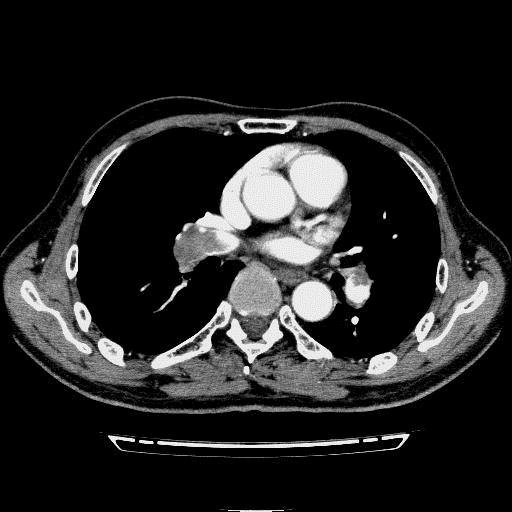

问题 病历摘要: 患者女性,83岁,活动后气促10天,伴心悸、咳嗽,咳少许白粘痰,感左侧胸痛,呈压榨样,与呼吸有关,但无放射痛,并发热,体温最高37.9℃,无明显规律性,无咯血、畏寒等。既往有系统性红斑狼疮病史,有吸烟史20年,已经戒烟20年。1月前始自觉双下肢易疲劳,但活动不受限。体查:T37.7℃,左肺可闻及啸鸣音和少许细湿啰音,心率123bpm,律齐,P2>A2,未闻及杂音。双下肢无水肿。 根据以上情况,还需要进一步做哪些检查?

选项 A.心电图 B.胸部CT平扫 C.胸部CT平扫+增强 D.心脏超声 E.肺通气灌注扫描 F.肿瘤指标五项 G.双下肢静脉超声

答案 ACDEG